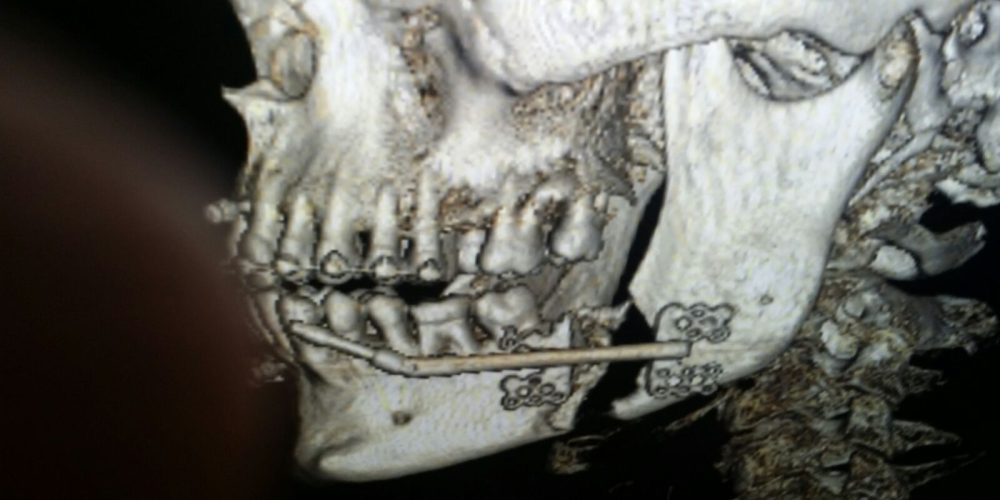

Categories Cirugía Maxilofacial Barcelona Posted on 04/06/2018 Paciente con apnea de sueño y mandíbula pequeña